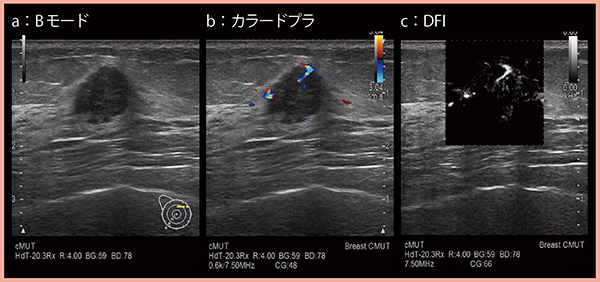

DFIは,これまで描出困難であった低流速の血流を表示する技術で,従来はアーチファクトを除去することで消えてしまっていた微細な血流を残し,より高分解能かつ高感度に描出可能となった。

図5は乳がん症例で,カラードプラ(b)にて貫入する血流が認められるが,DFI(c)ではより詳細に血流を評価できる。

図5 DFIによる微細血流の描出(乳がん)